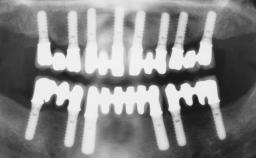

Conventional Loading of Six Implants in the Mandible and Final Restoration with a Full-Arch Metal-Ceramic FDP

# of Implants 6

Type of Implants One-Piece

Attachment One-Piece

Defining Characteristics Fully edentulous lower jaw to be rehabilitated with two or more implants

Modality > 4 implants, extending to mental nerve region